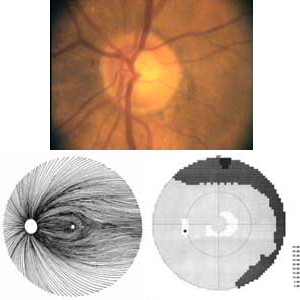

Výpadek proužku nervových vláken začíná temporálně dole od disku, kde je patrná peripapilární hemohagie. V zorném poli výpadku odpovídá horní paracentrální skotom.

Výpadek nervových vláken začíná temporálně dole, kde je na terči patrný zálom vény. Na barevné fotografii není viditelný, protože se jedná o výpadek v hlubší vrstvě nervových vláken, která je překryta vlákny neporušenými. Tato hluboká vlákna směřují do temporální dolní části makuly a v zorném poli jim odpovídá horní nasální skok.

Tento terč má exkavaci protaženou vertikálně a temporálně od obou pólu jsou patrné výpadky nervových vláken. V zorném poli se projevil výpadek vycházející z horní oblasti terče, kde je i peripapilární hemorhagie, jako skotom v nasální dolní části zorného pole s ostrou hranicí v horizontále.